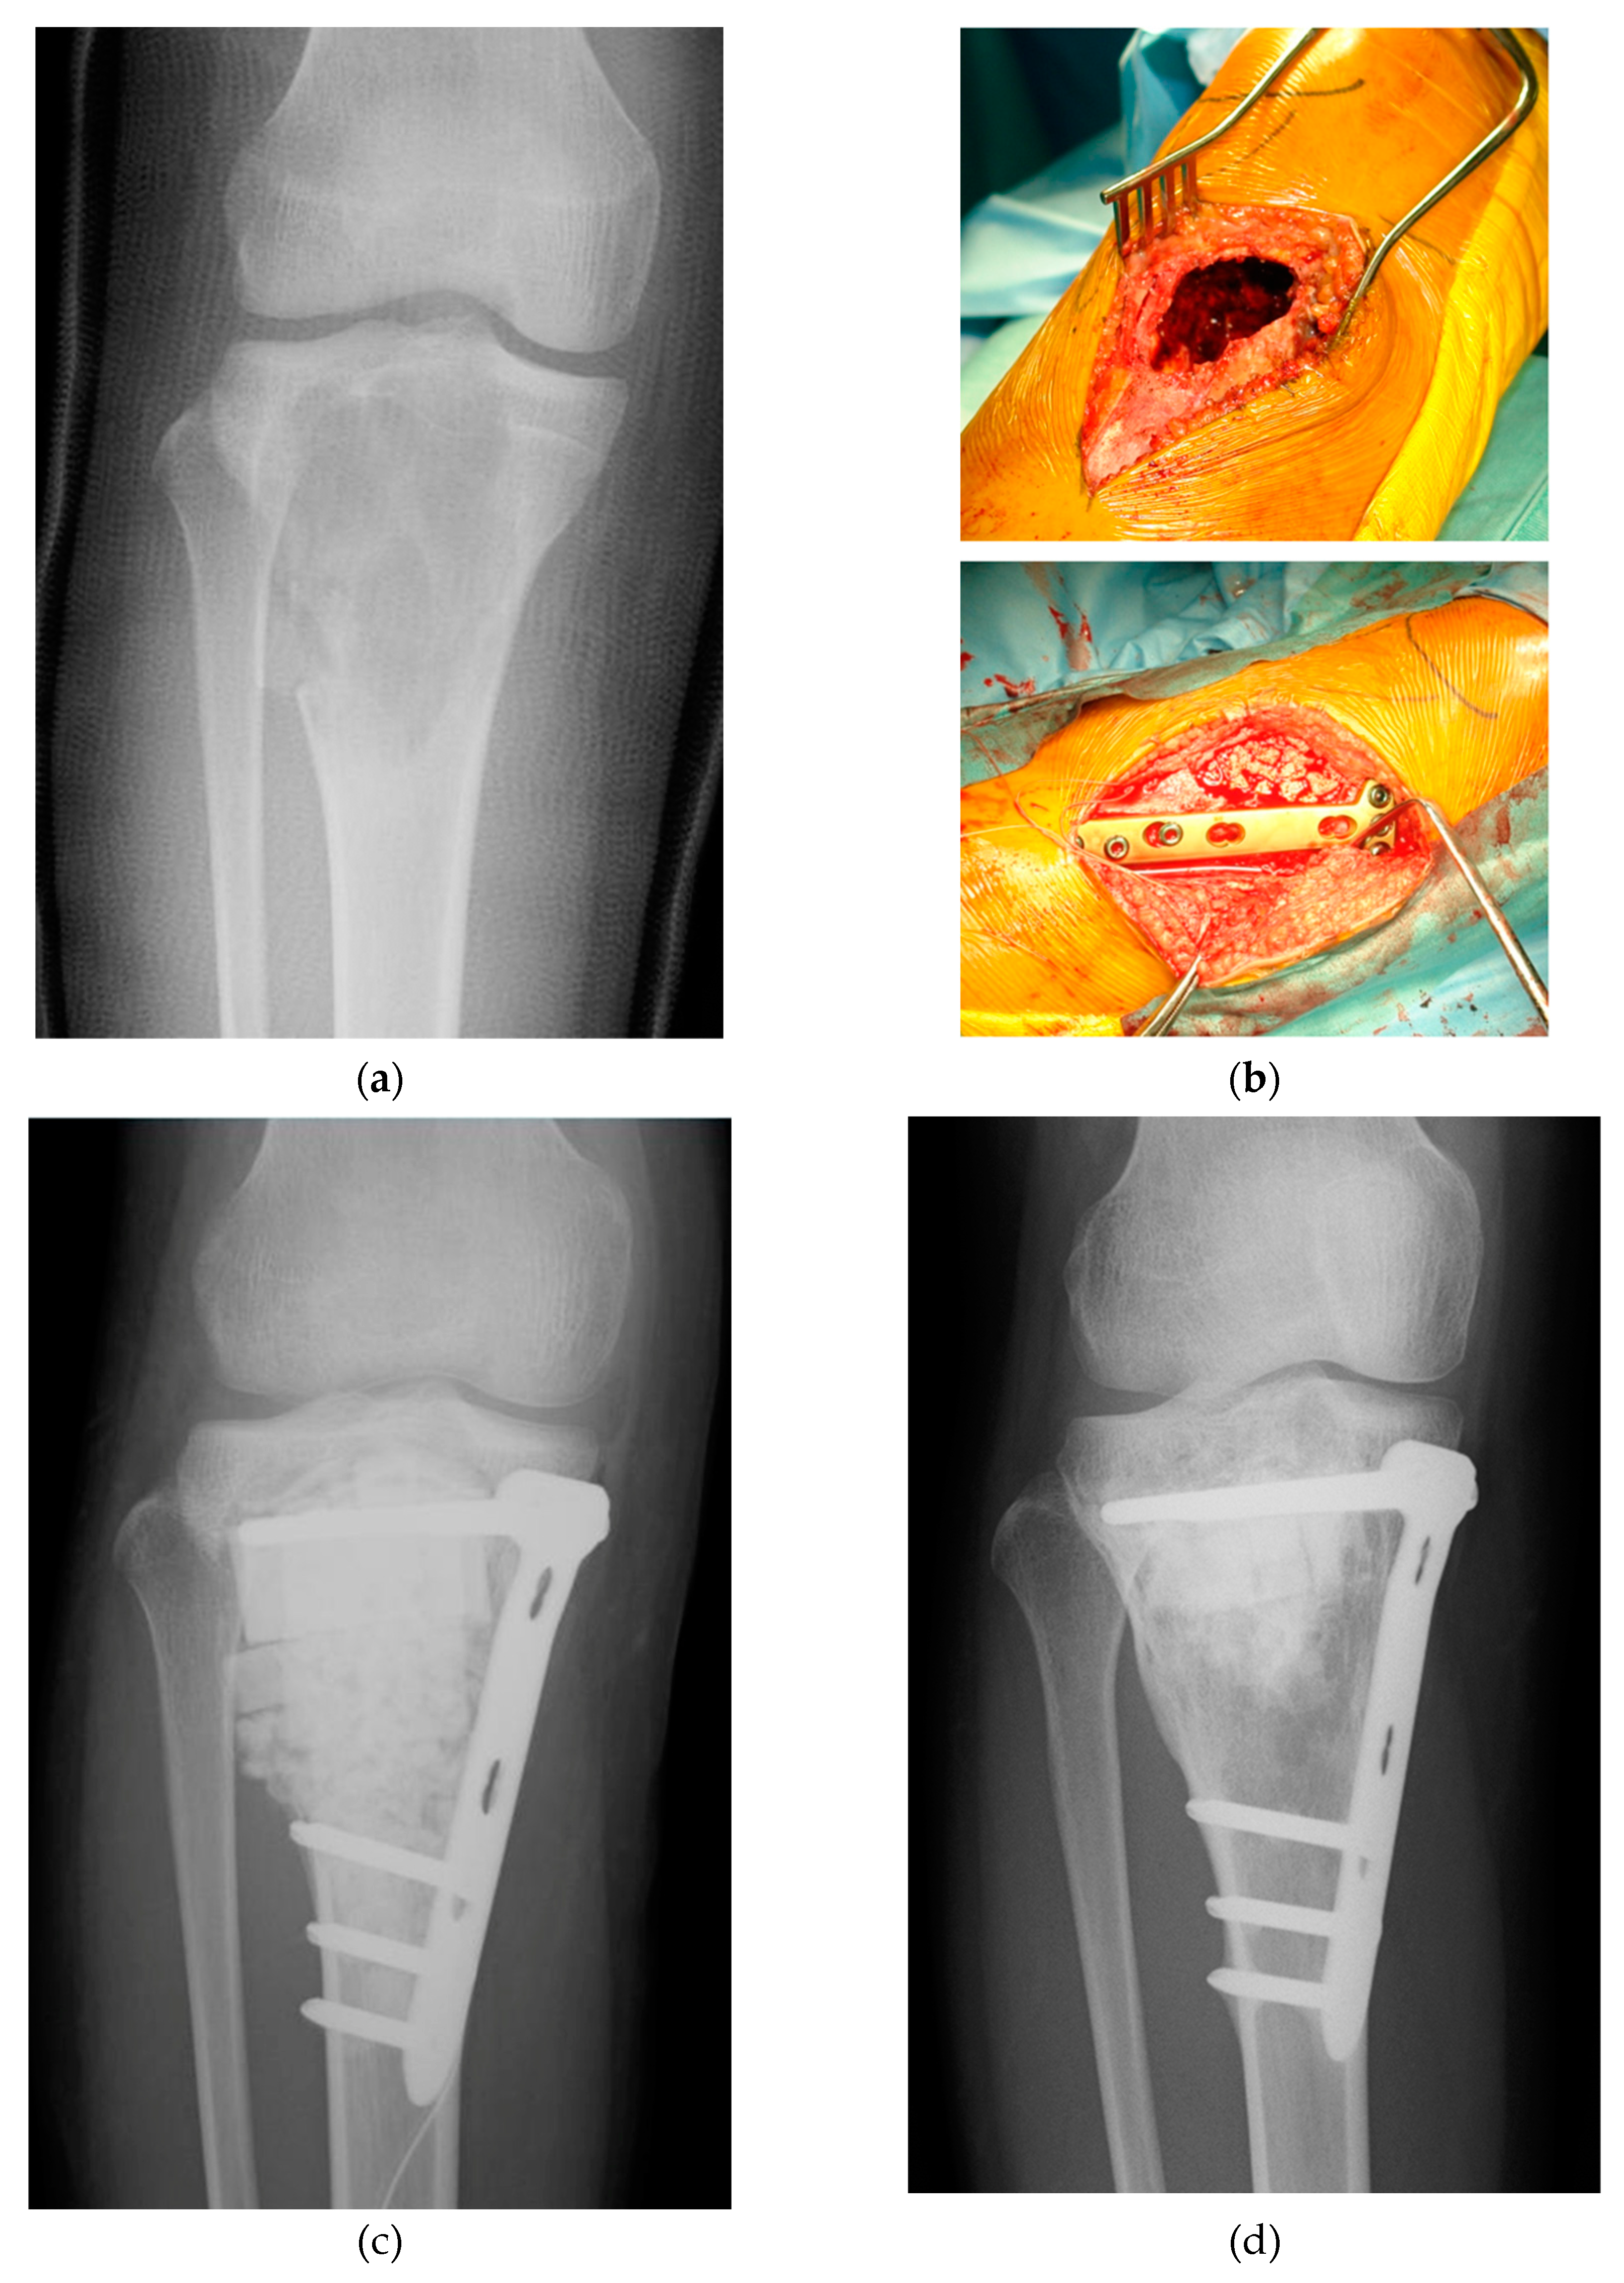

- Tanaka, T.; Kumagae, Y.; Saito, M.; Chazono, M.; Komaki, H.; Kikuchi, T.; Kitasato, S.; Marumo, K. Bone formation and resorption in patients after implantation of beta-tricalcium phosphate blocks with 60% and 75% porosity in opening-wedge high tibial osteotomy. J. Biomed. Mater. Res. B Appl. Biomater. 2008, 86, 453–459. [Google Scholar] [CrossRef] [PubMed]